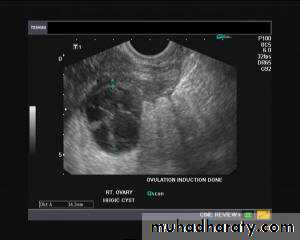

Hemorrhagic cyst of ovary resulting from Ovulation inductionThis young nulliparous female patient undwerwent ultrasonography following ovulation induction. The right ovary shows a typical hemorrhagic cyst formed from the corpus luteum. The first image (top row- left) is a transabdominal ultrasound image showing fine fibrinous strands within the cystic mass in the right ovary. Transvaginal ultrasound and color Doppler images confirm these findings. The uterus shows typical secretory changes in the endometrium suggesting post ovulatory phase.

Hemorrhagic ovarian cysts: